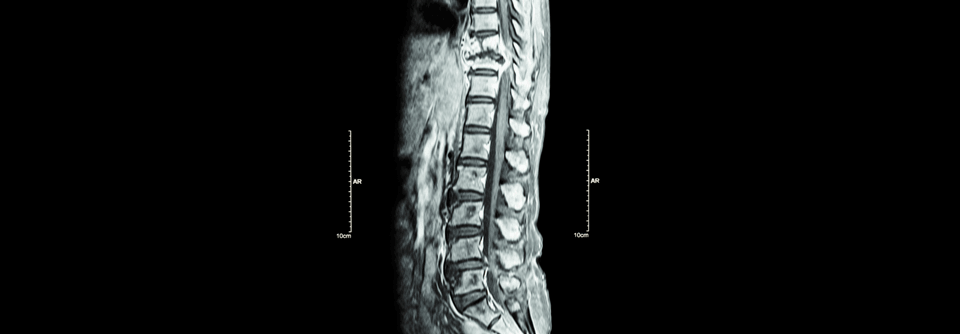

Ein Mann, viele Filiae: Knochenmetastasen in Oberarmen, Schultern, Rippen, Wirbelsäule, Becken und Femora. Ein Mann, viele Filiae: Knochenmetastasen in Oberarmen, Schultern, Rippen, Wirbelsäule, Becken und Femora. © Science Photo Library/ Camazine, Scott